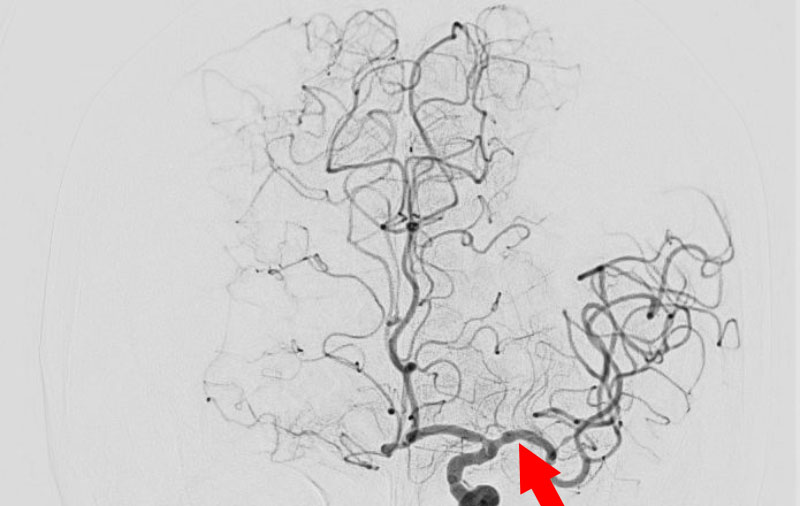

No.1596 手術中